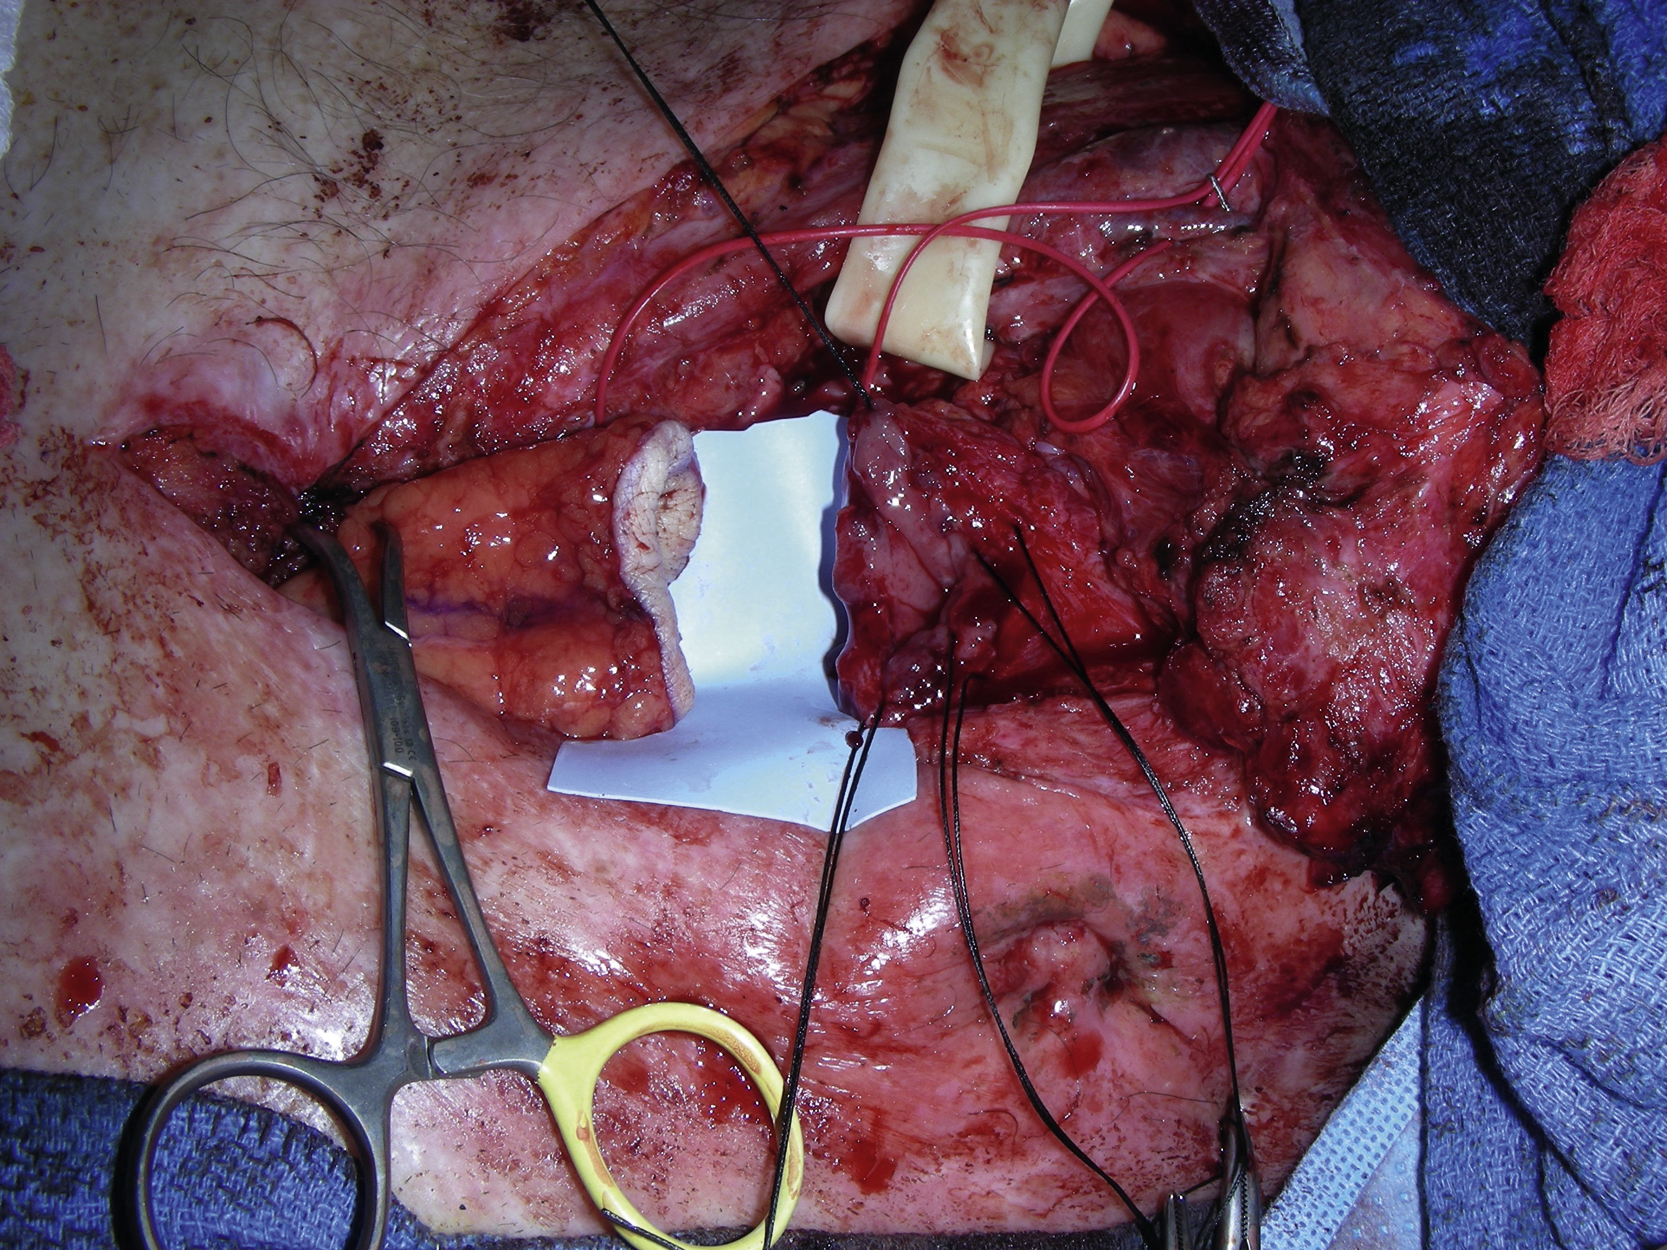

Once the colon and cervical esophagus had been prepared by the surgical oncology service for an anastomosis, the pedicle vessels of the radial forearm flap were divided proximally as far as possible ( Fig. 25.5 ). While waitfing for the flap inset and microvascular anastomoses, the fascial edges of the flexor carpi radialis and the brachial radialis were approximated with running 3-0 Vicryl suture and the loose skin around the periphery of the wound was fixed with 3-0 Vicryl suture, reducing the overall size of the wound to 17 × 7 cm for a skin graft placement ( Fig. 25.6 ). A split-thickness skin graft at 0.015 thickness was harvested from the left thigh with a dermatome. It was placed on the forearm wound as a sheet graft and stapled to the periphery of the wound edge. A volar forearm splint was placed for immobilization.

The colonic stump to the flap was anastomosed by the surgical oncology service ( Fig. 25.7 ). The flap was then tunneled under the sternum by the plastic surgery service and the flap to the cervical esophagus anastomosis was again performed by the surgical oncology service ( Fig. 25.8 ). The right transverse cervical artery was dissected out. A branch of the right external jugular was also dissected out. Both vessels were prepared for microvascular anastomoses. However, the right transverse cervical artery was found to have poor blood flow and the right inferior thyroid artery was therefore selected instead and dissected out for microvascular anastomosis. The artery was also tunneled under the right external jugular vein. The arterial microanastomosis was performed with interrupted 8-0 nylons in an end-to-end fashion. The venous anastomosis was performed with a 3-mm coupler device in end-to-end fashion between the donor cephalic vein and a branch of the right external jugular vein ( Fig. 25.9 ).